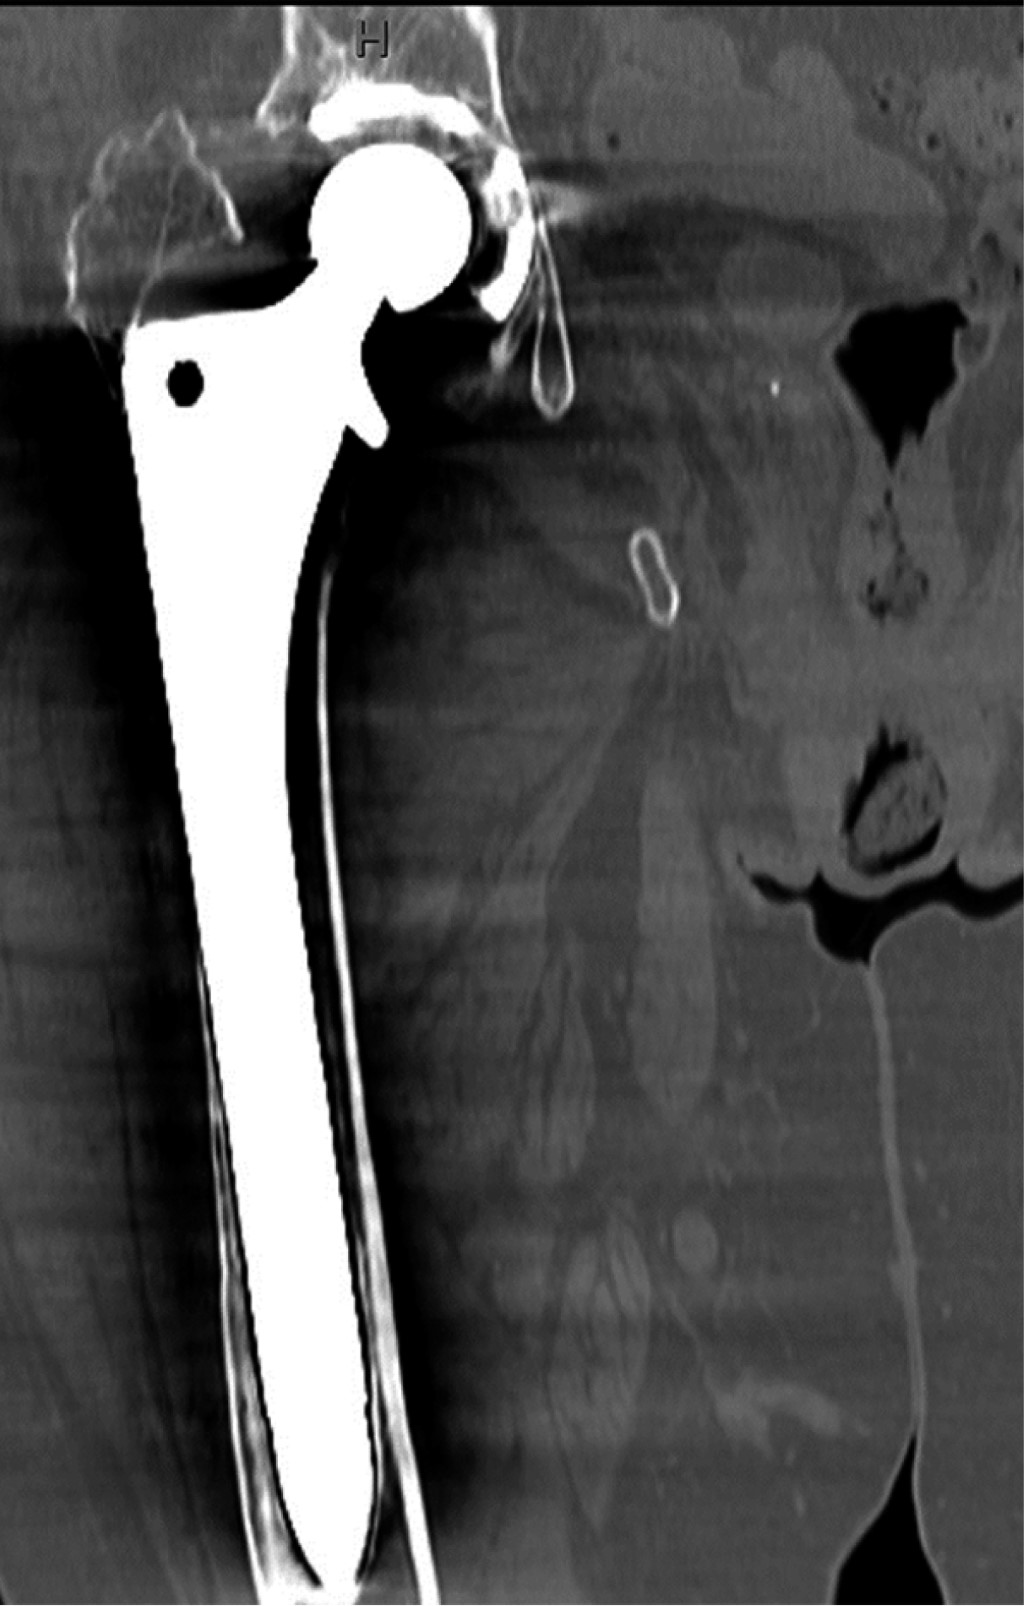

Minimizing risk: evaluation of the relationship between femoral stem loosening and the risk of presenting with peri-prosthetic hip fracture

Introduction: evaluation of predictors of periprosthetic fracture in loosened femoral stems. Material and methods: retrospective case-control study comparing aseptic loosened stems in two groups: cases: patients who experienced periprosthetic femoral fracture before replacement could be performed (n = 9). Controls: experienced prosthetic replacement without fracture (n = 19). Results: pain intensity (VAS) was the most important aspect (p = 0.01), predominating in the controls. The simple radiological parameters did not show statistically significant findings predictive of peri-prosthetic fracture (number of Gruen zones, sum of them in mm, stress shielding, pedestal, polyethylene wear, stem subsidence). The role of complementary tests (CT and scintigraphy) for the definitive diagnosis of loosening was relevant, but not significant. The type of implant showed no differences. Overall implant survival was higher in cases than in controls (p = 0.016). This difference continues when comparing each loosened stem until fracture or replacement (p = 0.024). Conclusion: the main factor protecting against fracture is the replacement of a stem with clinical and radiological diagnosis of loosening. Adequate follow-up of the patient plays a determining role in this, especially when considering the greater intensity of pain in the controls, which used to guide surgeons to perform replacements before the fracture occurred. This is reinforced if we take into account that up to one third of the cases did not have regular check-ups, and therefore did not have the opportunity for replacement prior to the fracture. The role of complementary tests (CT and scintigraphy) is also very important, taking into account the low diagnostic yield obtained from simple X-rays.

Figure 1